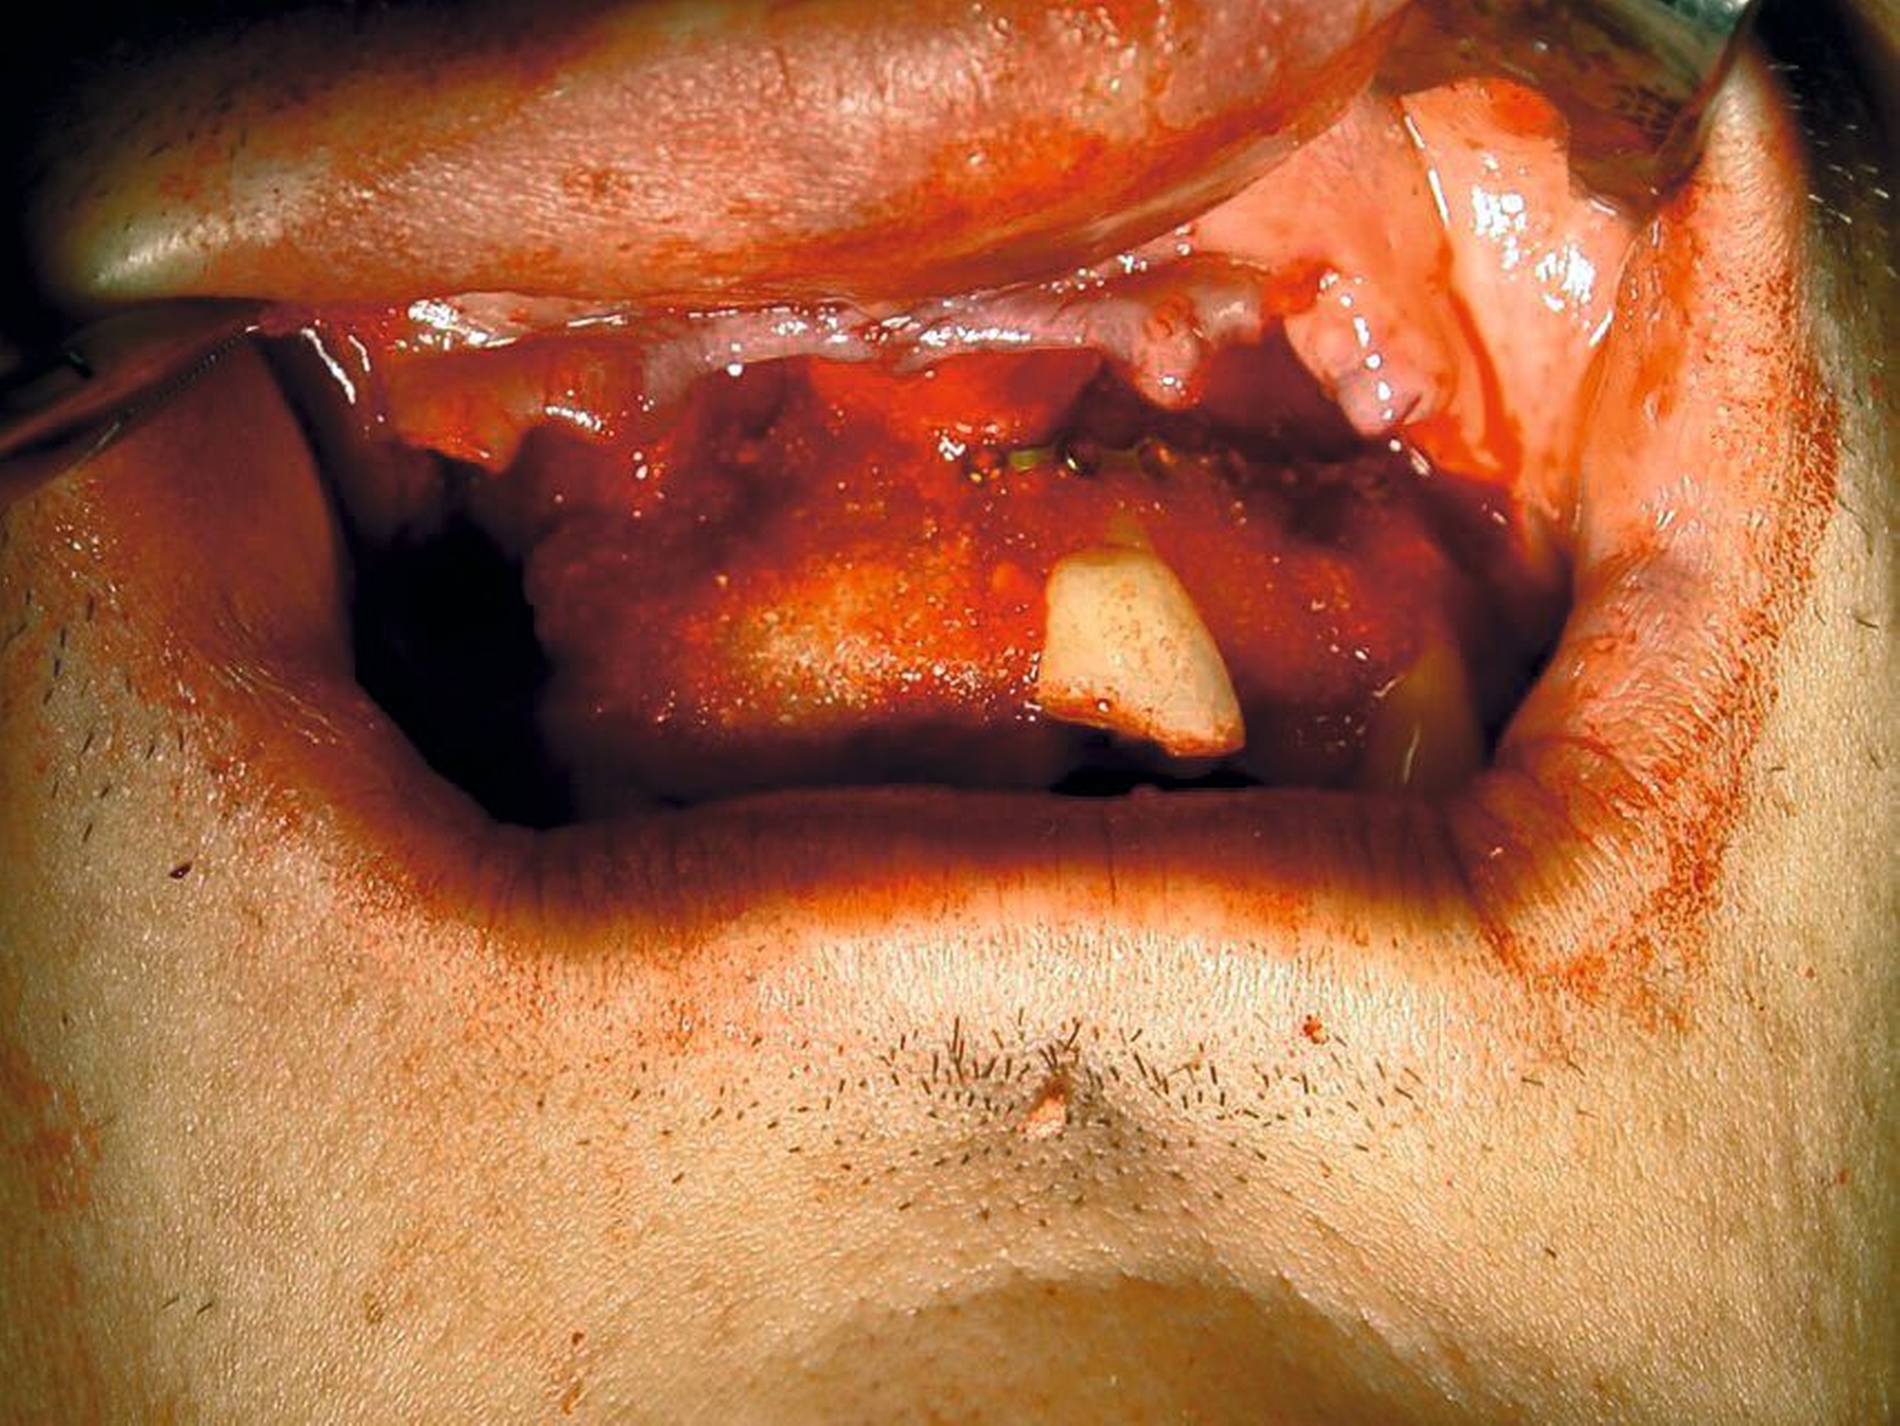

Eine Dekoronation ist eine chirurgische Intervention, die durchgeführt werden kann, wenn aufgrund ausgeprägter Schädigungen der desmodontalen Zellen und der Wurzeloberfläche eine Resorption auftritt. Im Rahmen der klinischen Untersuchung imponiert der betroffene Zahn aufgrund der Ankylose mit einem metallischen (hellen) Klopfschall. Röntgenologisch lassen sich Resorptionslakunen an der Wurzeloberfläche erkennen. Bei progressiver Resorption und Infraposition des betroffenen Zahnes in Relation zur Restdentition kann eine Dekoronation indiziert sein [Malmgren et al., 2015] (Abbildung 2).

Das Ziel der Dekoronation ist es, die klinische Krone unter Belassung der resorbierenden Wurzel zu entfernen, damit der Alveolarknochen aufgrund der Knochenneubildung bei Ersatzresorption erhalten und eine optimale Voraussetzung für spätere Interventionen gegeben werden kann [Malmgren et al., 2006]. Bei Patienten im Wachstum kann die Dekoronation eine sinnvolle Therapieoption darstellen, um den teils erheblichen Knochenverlust in Verbindung mit der chirurgischen Entfernung der ankylosierten Zahnwurzel zu vermeiden (Empfehlung 60).